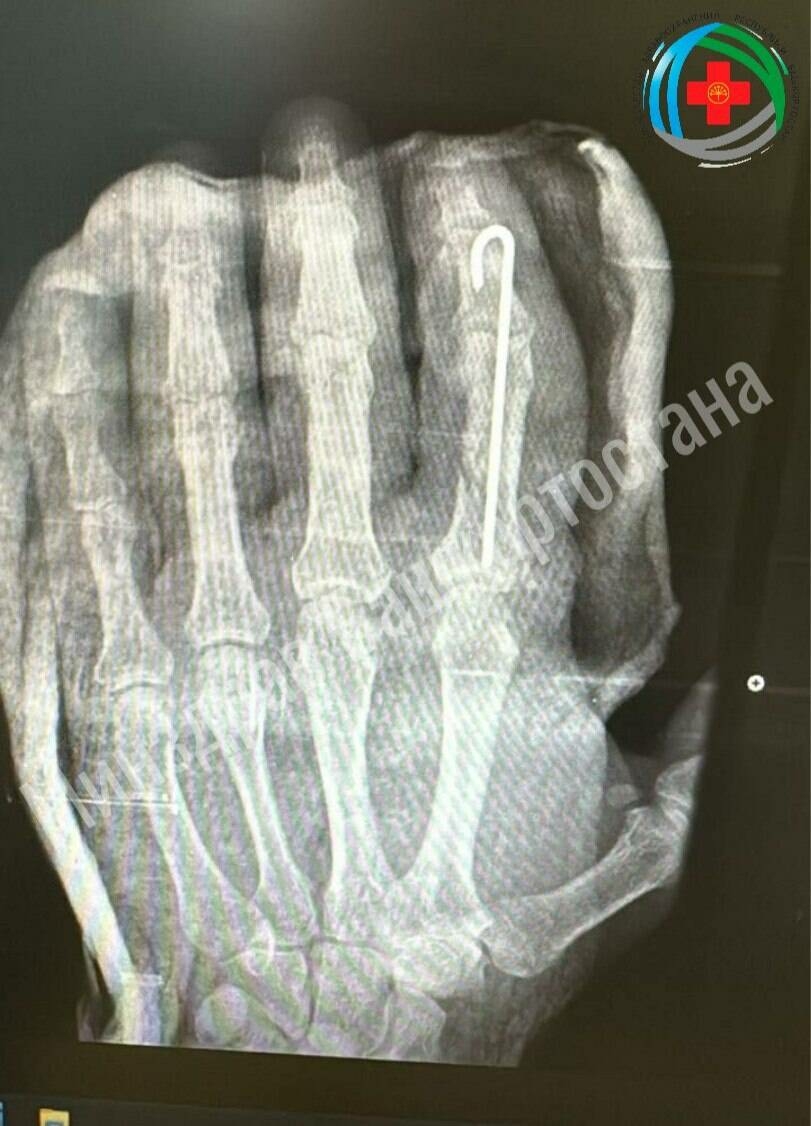

Фото: Башкортстан Сәламәтлек саклау министрлыгы матбугат хезмәте

Башкортстанның Благовещенск районында табиблар ир-атның чабып өзелгән бармагын коткара алган. Бу хакта «Башинформ» яза.

Республика Сәламәтлек саклау министрлыгында хәбәр итүләренчә, ир-ат кул бармагын ялгыш балта белән чапкан. Хирурглар ашыгыч рәвештә операция ясарга карар кылган.

Белгечләр чын мәгънәсендә ювелирларча эш башкарган. Табиблар, кан әйләнешен яңарту өчен, бик вак кан тамырларын торгызган, сөякләрне төгәл итеп ялгаган һәм бармакның элеккечә хәрәкәтләнү сәләтен саклап калу өчен йомшак тукымаларны реконструкцияләгән.

Бармак төзәлә. Ир-ат аны хәтта бераз селкетә ала башлаган. Хәзер ул дарулар белән дәвалана, физиотерапия уза һәм дәвалау физкультурасы ясый. Нәтиҗәдә бармакның барлык функцияләре тулысынча торгызылырга тиеш, дип көтә табиблар.